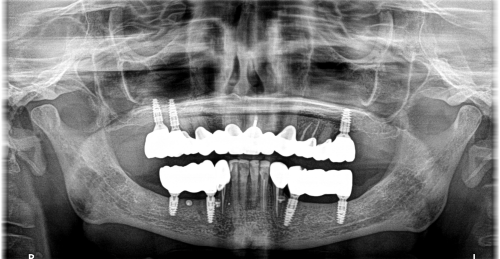

Wykonana praca protetyczna:

- korony pełnoceramiczne na zębach własnych górnych

- korony na implantach w miejscach braków zębów górnych

- mosty na implanatch w łuku dolnym

- odbudowa flow-injection zębów dolnych przednich